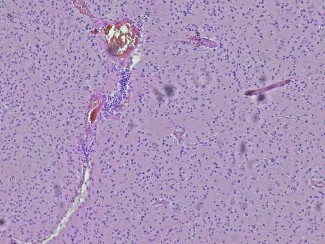

The association’s support has focused on the GLIOTEX project, which opens up promising prospects in the treatment of brain tumours. This research project is based on the use of innovative experimental models based on tumour cells directly from patients.

marquage multiplex de lymphocytes dans un échantillon de tumeur cerebrale